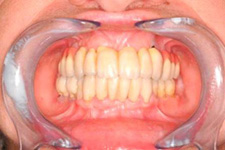

S pomocí zubních implantátů můžeme díky různým kotevním systémům (třmeny, kulové hlavy, Locatory) zajistit stabilitu a držení protézy nebo při použití většího počtu implantátů zhotovit pevné náhrady – můstky nalepené nebo našroubované na pevno na implantáty.

S těmito typy náhrad můžeme dosáhnout perfektní funkci, výbornou estetiku, fonetiku a současně zajistit u pacienta možnost dobré hygienickou péče a čištění, která je pro životnost implantátů velice důležitá.

Implantáty jsou osvědčeným a vyzkoušeným řešením, které dnes umožňuje zhotovení estetické a funkční náhrady.

• Dokonalé obnovení funkce a estetiky